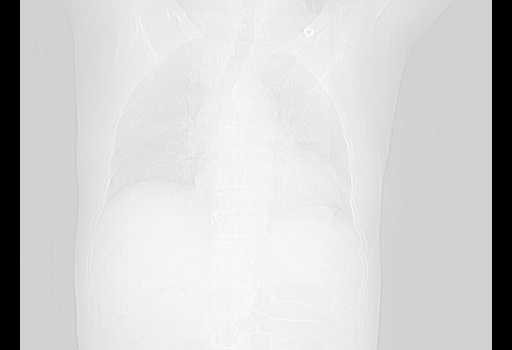

甲强龙80mg/日+抗结核治疗(异烟肼+利福霉素+乙胺丁醇)10天。复查肺部CT。

治疗10天肺部CT

94186 3 1 .bmp

94186 3 2 .bmp

94186 3 3 .bmp

94186 3 4 .bmp

94186 3 5 .bmp

94186 3 6 .bmp

94186 3 7 .bmp

94186 3 8 .bmp

94186 3 9 .bmp